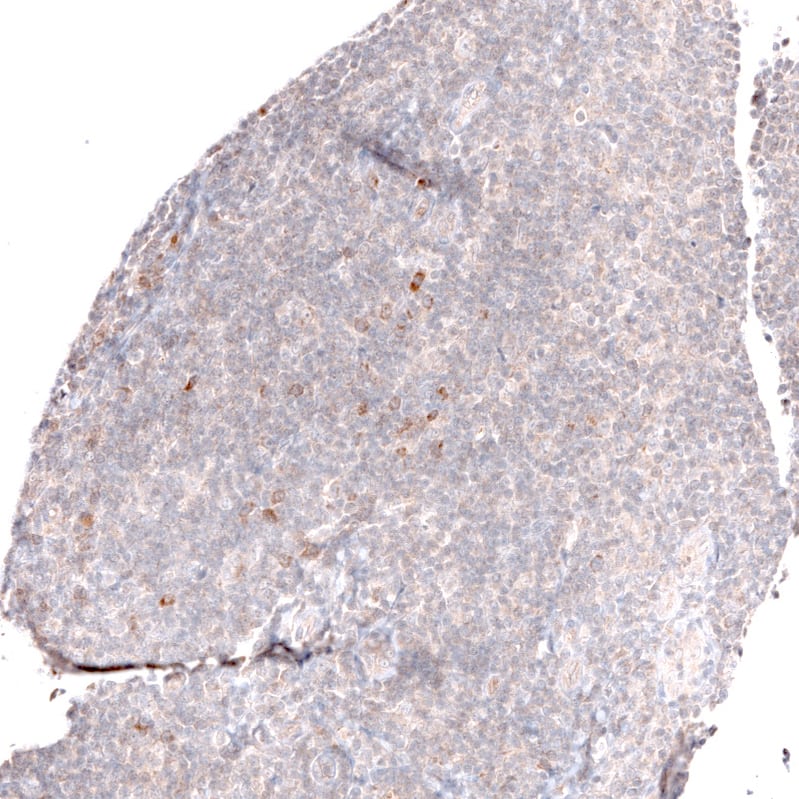

Staining of human tonsil shows mainly very weak positivity in non-germinal center cells.